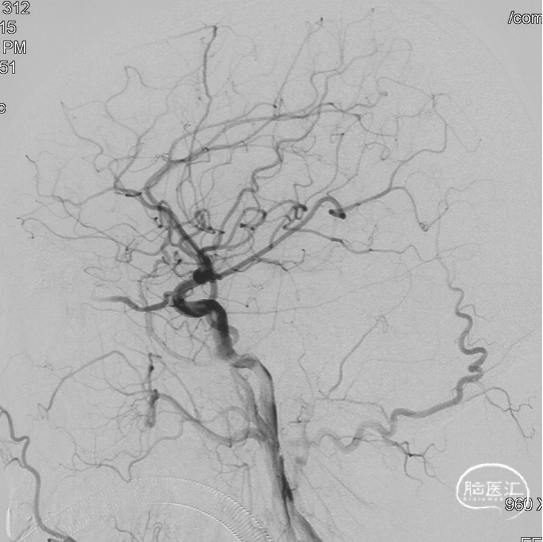

术前造影

双侧颈内动脉正侧位造影见前颅窝底硬脑膜动静脉瘘,双侧筛前动脉、筛后动脉向瘘口供血,通过皮层静脉向上矢状窦引流。

双侧颈外动脉正侧位造影见镰前动脉向瘘口供血。

前颅窝底DAVF,由镰前动脉、双侧筛前、筛后动脉参与供血,通过皮层静脉向上矢状窦引流,引流静脉伴有瘤样扩张,Cognard IV型、Borden III型。由于脑膜中动脉-镰前动脉路径较为迂曲,超选困难,引流静脉迂曲扩张,预计到达瘘口起始端存在困难,决定经眼动脉-筛前动脉栓塞。